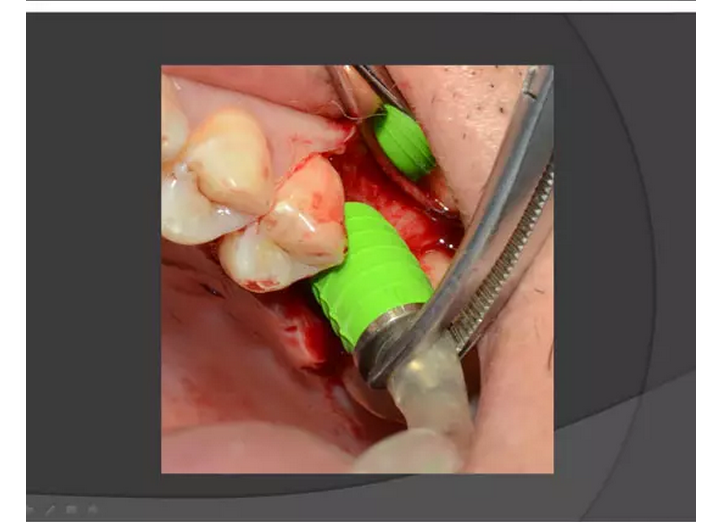

【KQ88口腔網(wǎng)?!可项M竇種植手術(shù)概述——王漢禹

上頜竇種植手術(shù)概述

王漢禹